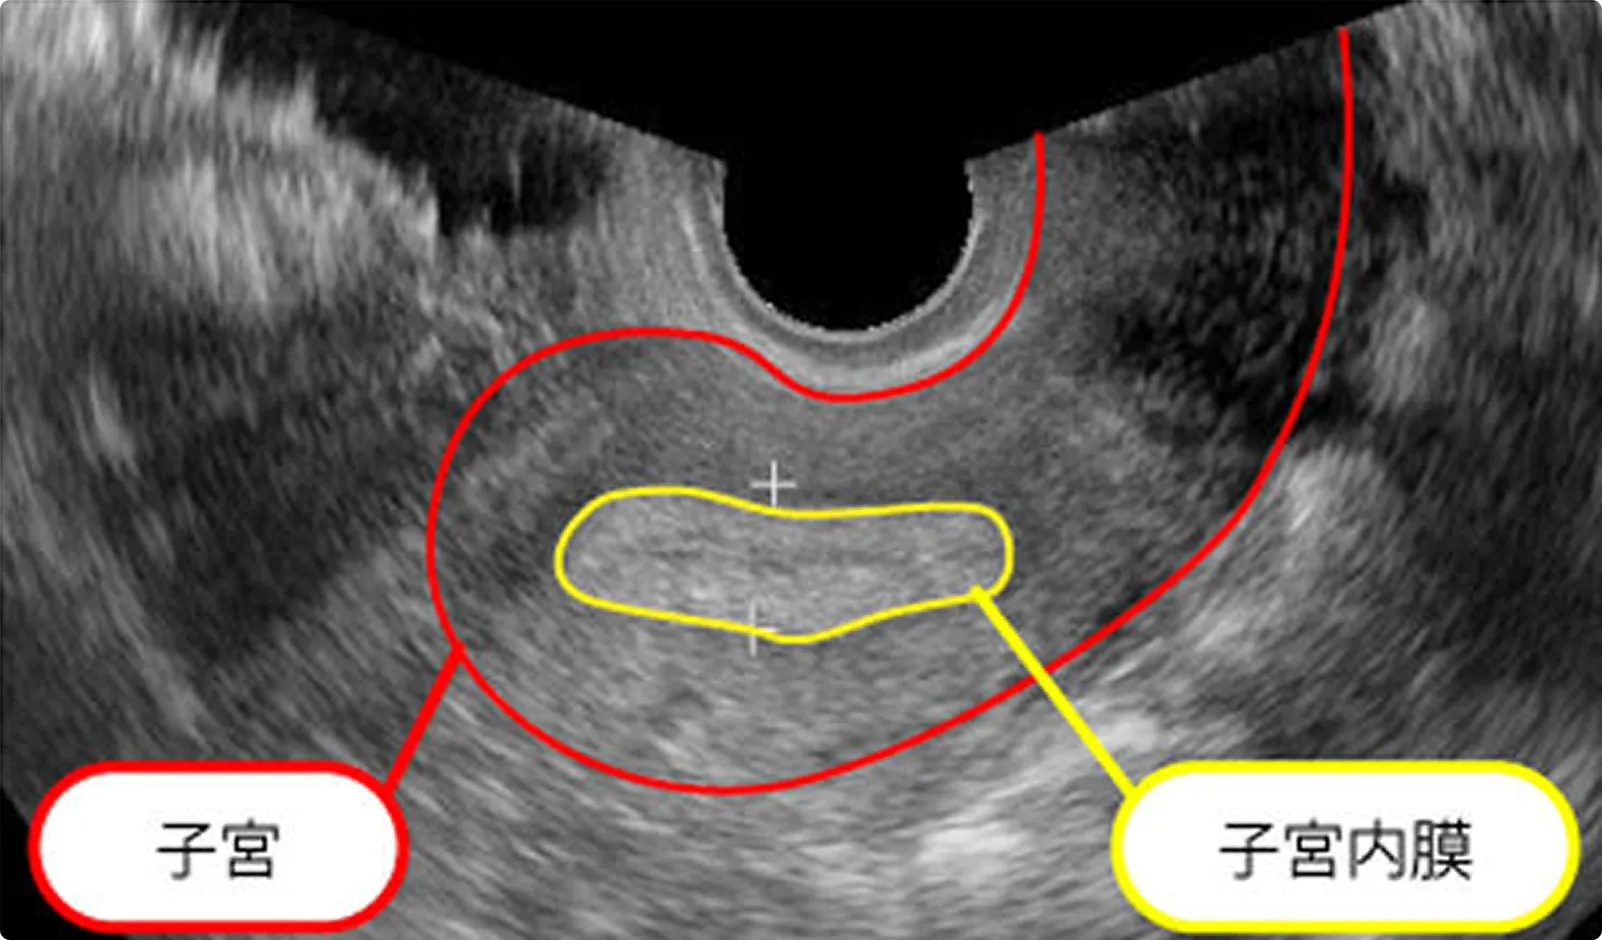

排卵後

排卵後の子宮内膜

間質浮腫が進み白く見えます。

排卵後の黄体

排卵後は上記のように黄体を形成するか、画面上主席卵胞がはっきりしなくなります。